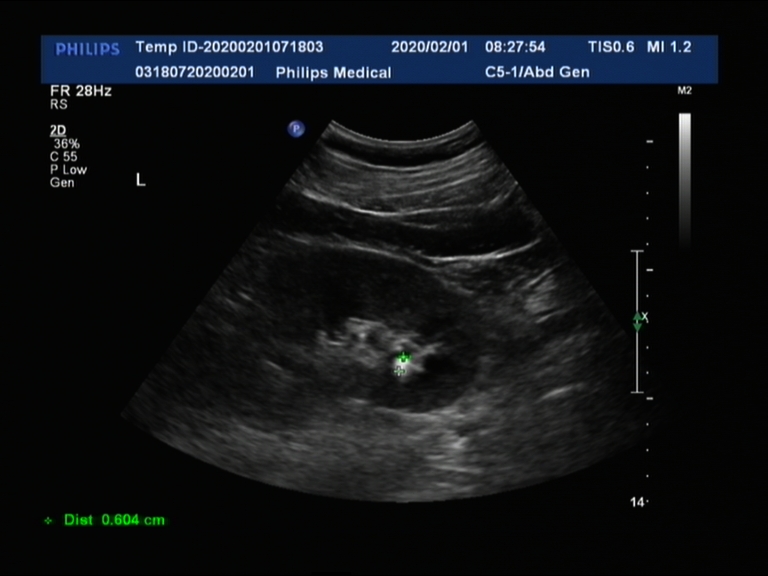

白色亮点就是肾结石

1. 结石直径0.5~1cm,其中以0.6cm为适宜;